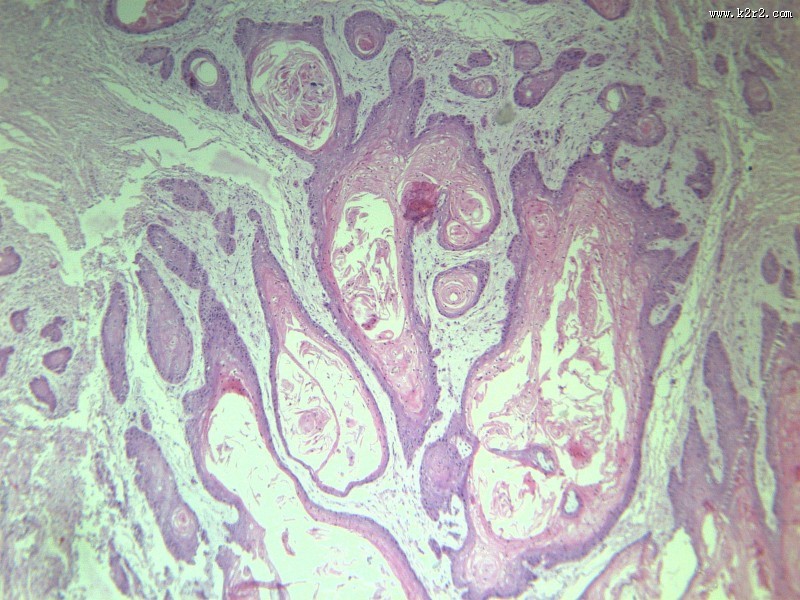

首页 > 其他类别 > 高分化鳞癌(12张) > 高分化鳞癌 第1张

高分化鳞癌 - 第1张